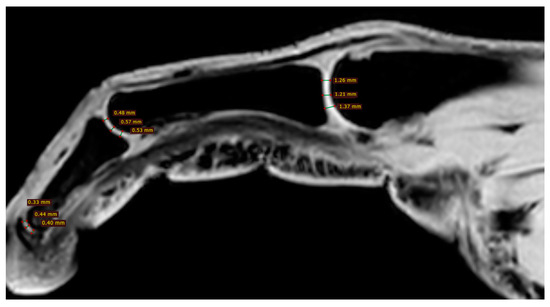

2.4. Magnetic Resonance Imaging

Cartilage Thickness and Distal Phalanx Length in MRI